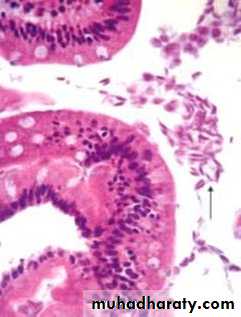

Clostridium difficile colitis. A, The colon is coated by tan pseudomembranes composed of neutrophils, dead epithelial cells, and inflammatory debris (endoscopic view). B, Pseudomembranes . C, Typical pattern of neutrophils emanating from a crypt is reminiscent of a volcanic eruption

PSEUDOPOLYPSCrypt Abscess

Ulcerative Colitis